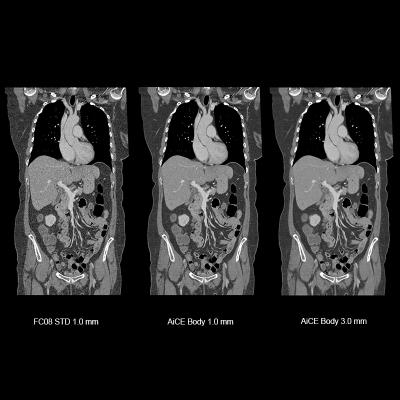

Image courtesy of Canon Medical Systems

October 21, 2019 — Canon Medical Systems USA Inc. has received U.S. Food and Drug Administration (FDA) 510(k) clearance on its Advanced Intelligent Clear-IQ Engine (AiCE) for the Aquilion Precision computed tomography (CT) system. The clearance further expands access to Canon’s new deep convolutional neural network (DCNN) image reconstruction technology. This technology, now available on both the Aquilion Precision and Aquilion One/Genesis Edition premium CT systems, uses a deep learning algorithm to differentiate signal from noise so that it can suppress noise while enhancing signal, forging a new frontier for CT image reconstruction.

Aquilion Precision, which Canon calls the world’s first ultra-high resolution CT, provides two times the resolution of conventional CT, revealing detail that is typically only seen in cardiac catheterization labs. With AiCE, the system now enables clinicians to perform super-high resolution studies at doses equivalent to standard resolution CT (with traditional hybrid iterative reconstruction techniques). AiCE learns from the high image quality of model-based iterative reconstruction (MBIR) to reconstruct CT images with improved high contrast spatial resolution.